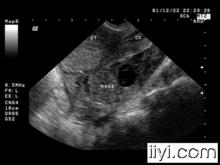

鏡下黃體黃體存在時間多少,視排出的卵受精與否,若卵子未受精,黃體僅維持二周開始退化,退化時黃體細胞逐漸萎縮變小,周圍結締組織及成纖維細胞侵入黃體,逐漸由結締組織所代替結疤所代替,組織纖維化,外觀色白, 即白體(corpusalbicans);若卵子受精成功並開始妊娠,黃體繼續增長,至妊娠2~3月後慢慢萎縮。